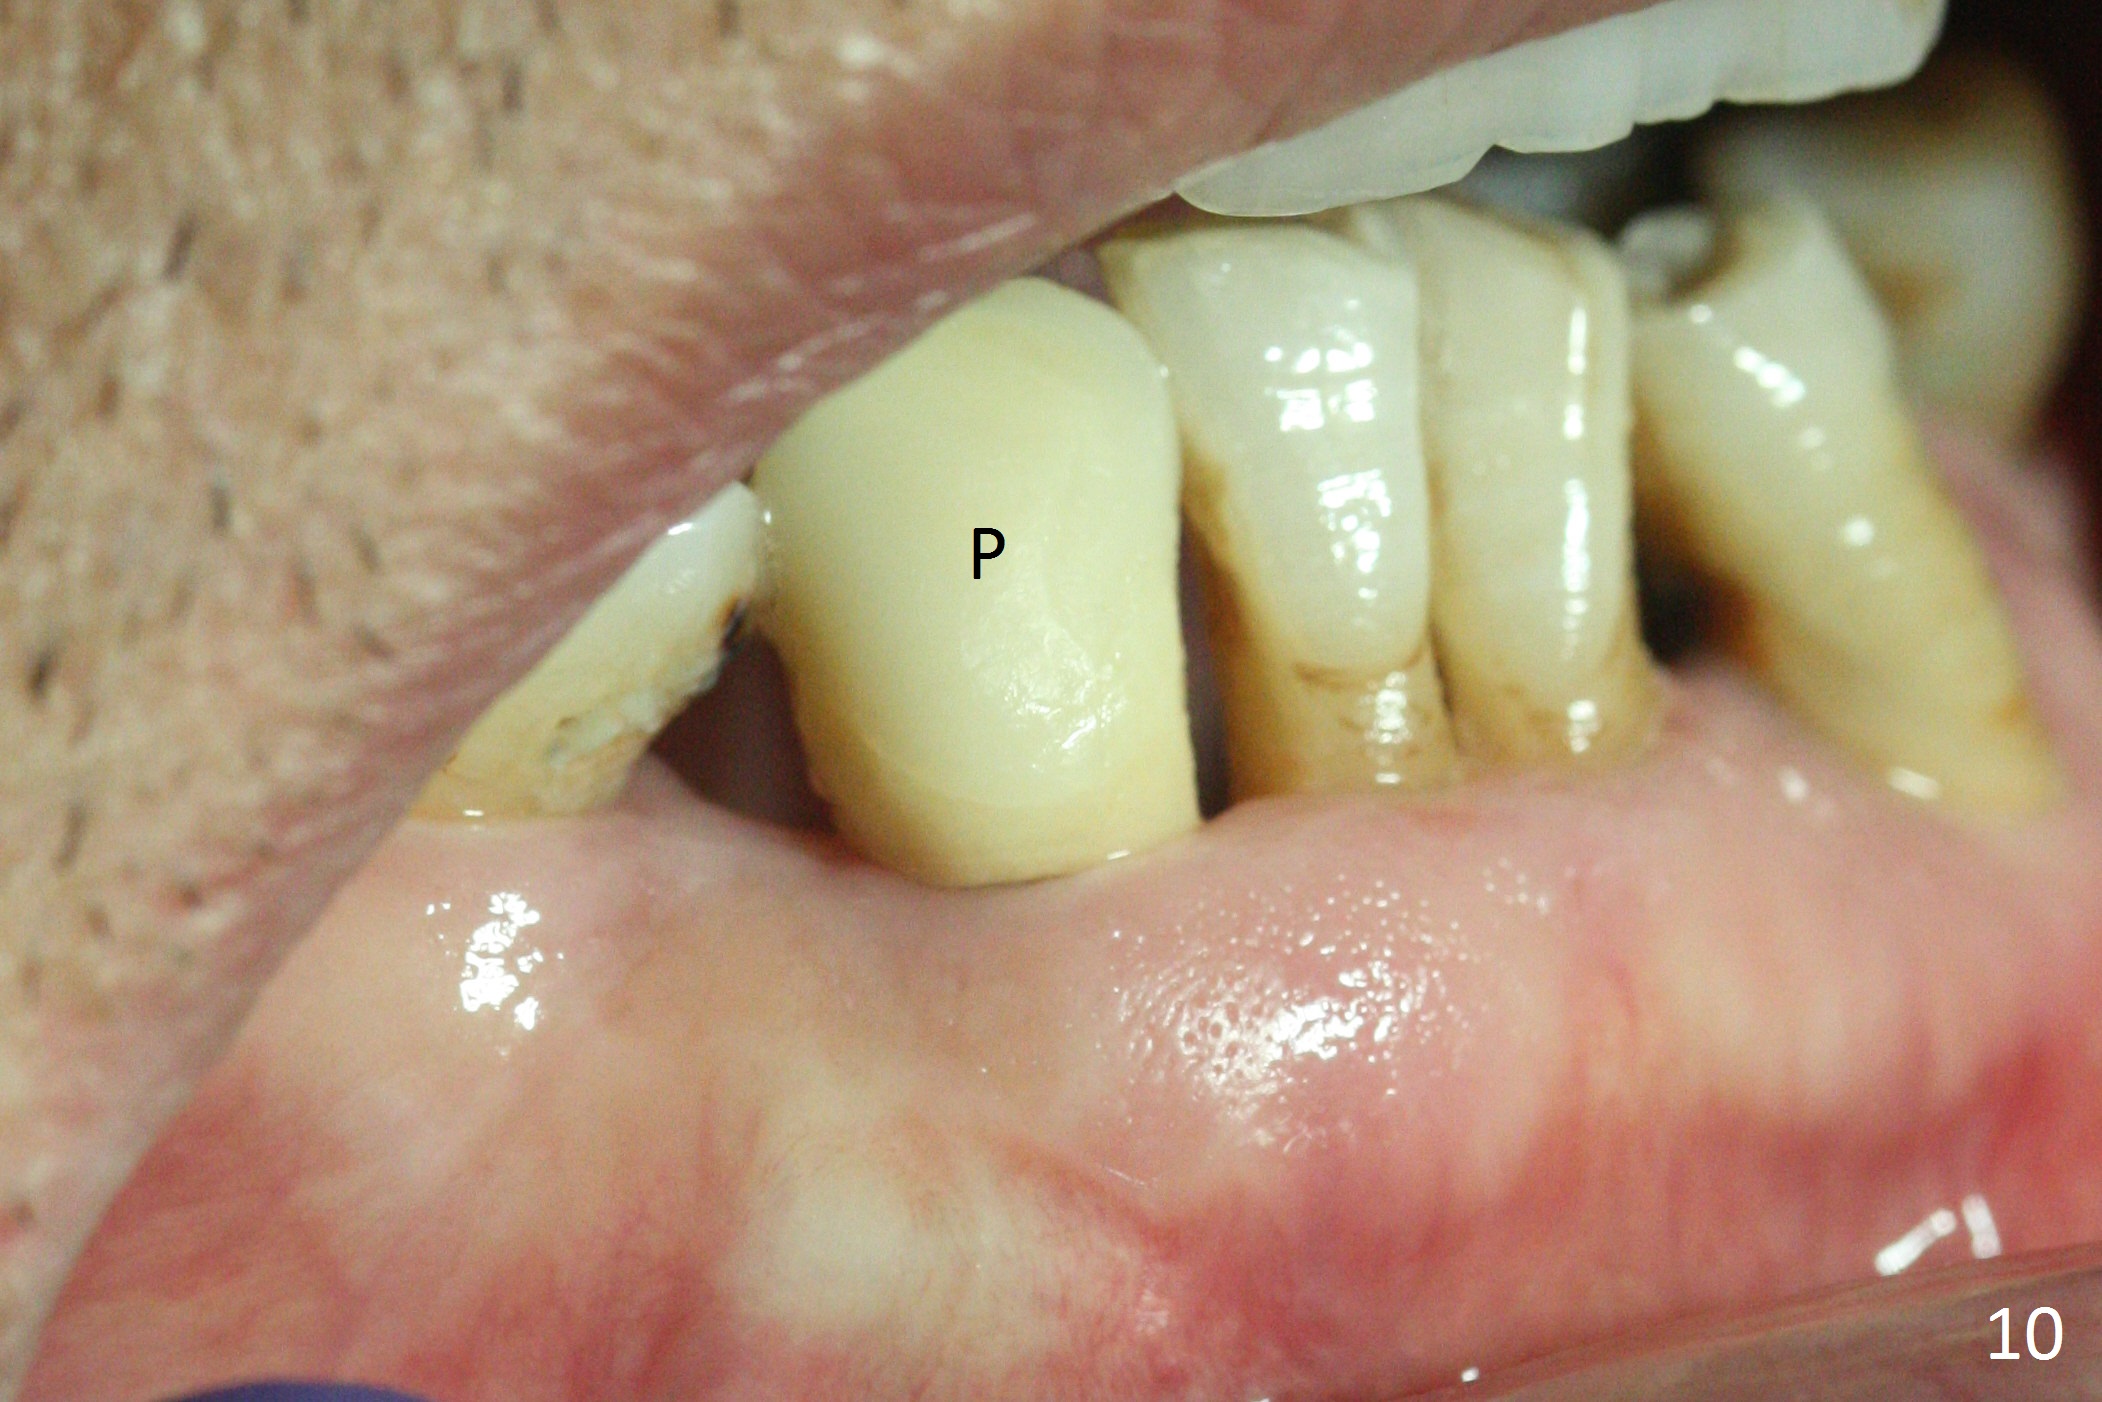

The lower dentition is special, consisting of a residual root (Fig.1 ^), 2 incisor (I), 1 canine (C), 1 premolar (P) and 1 molar (M). The residual root looks like an incisor with rotation of 90º (Fig.2,3). Osteotomy is initiated (Fig.4) for a 3x16(2) mm 1-piece implant (Fig.5 with 45 Ncm). The implant is being placed as distal as possible (Fig.4 arrow) so that a large canine-like provisional is to be fabricated in the large edentulous space (Fig.8,9) after bone graft (Fig.6,7 *). The gingiva around the provisional (Fig.10 P) remains healthy 11 days postop with occlusal clearance against the opposing dentition (Fig.11). The implant threads are not exposed with the help of bone graft 3 months 1 week postop (Fig.12). The gingiva around the implant is healthy (Fig.13). Soft tissue socket is formed by the provisional (Fig.14 *).